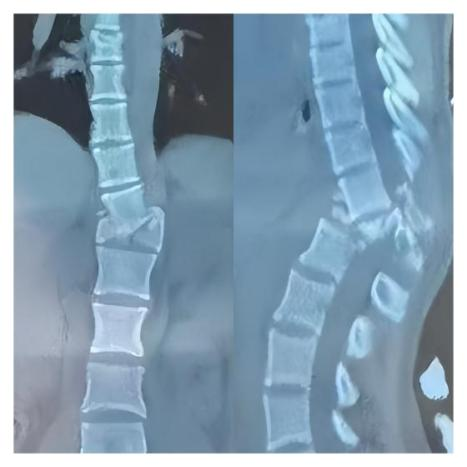

下面这张影像,展示的是一位脊髓损伤患者的脊柱CT——椎体破碎,严重错位。看到这样的影像,我们对于她脊髓功能的恢....